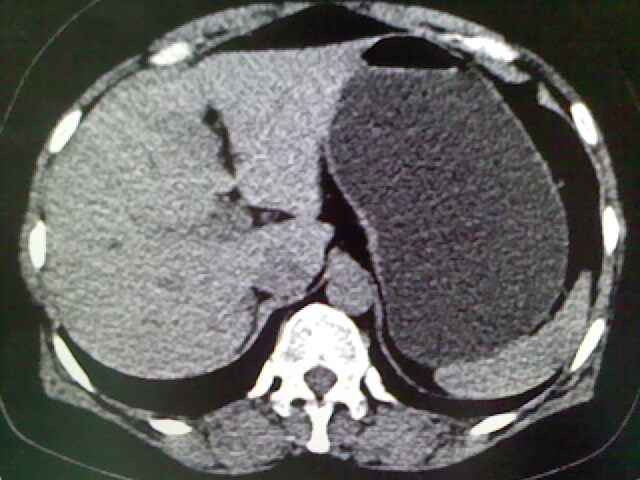

以下是引用卜一在2009-4-2 13:26:00的发言:[br]胆囊颈部结石伴胆囊炎!另:建议增强,待除外肝内占位及胆囊占位!

以下是引用liaoqiang在2009-4-2 16:23:00的发言:[br]胆囊是否切除?胆囊颈区致密影考虑金属夹?结石?肝脏右叶低密度影,考虑增强。